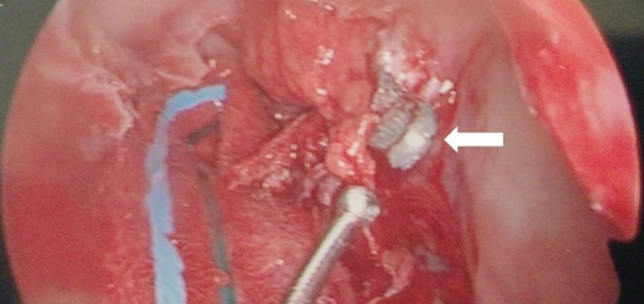

Trans-sinus endoscopic removal of retrobulbar air gun pellet within the orbital apex

Muzammil A Nahaboo Solim

,

Mike McKenna

Gar-Yun Wong

Sreekumari Pushpoth

David EJ Whitehead

·

2nd August 2022